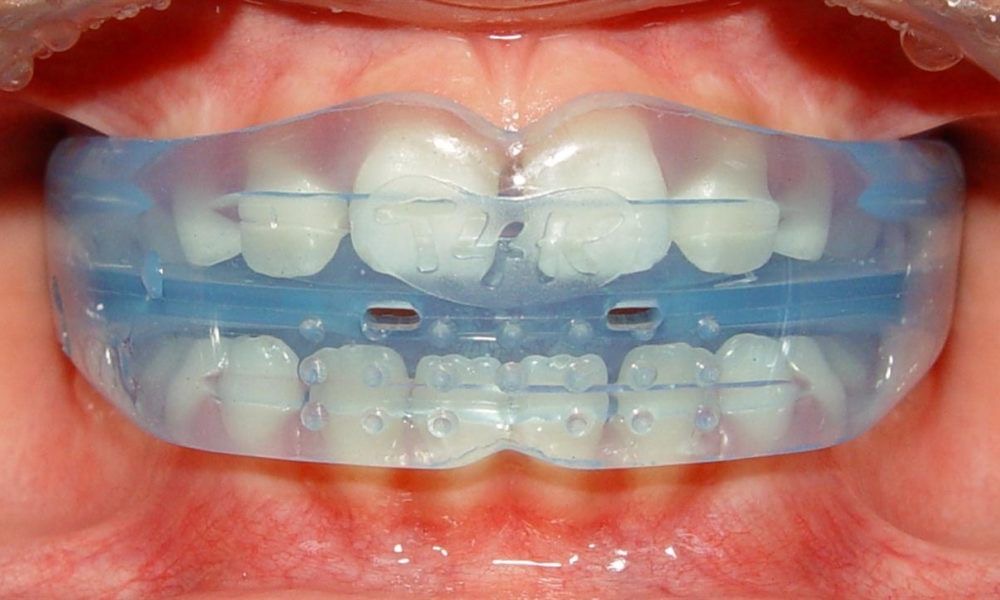

Our Treatments

Preventive & Restorative Dentistry

Cosmetic Dentistry